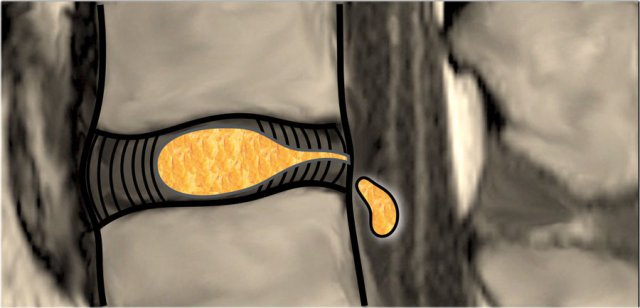

Disc Protrusion versus Extrusion Disc Protrusion versus Extrusion

Protrusion - Extrusion

Protrusion indicates that the distance between the edges of the disc herniation is less than the distance between the edges of the base.

Extrusion is present when the distance between the edges of the disc material is greater than the distance at the base.

Extrusion is associated with a defect in the annulus fibrosus and are usually noncontained.

Migration indicates displacement of disc material away from the site of extrusion, regardless of whether sequestrated or not.

Sequestration

The term sequestration is used to indicate that the displaced disc material has lost continuity with the parent disc.